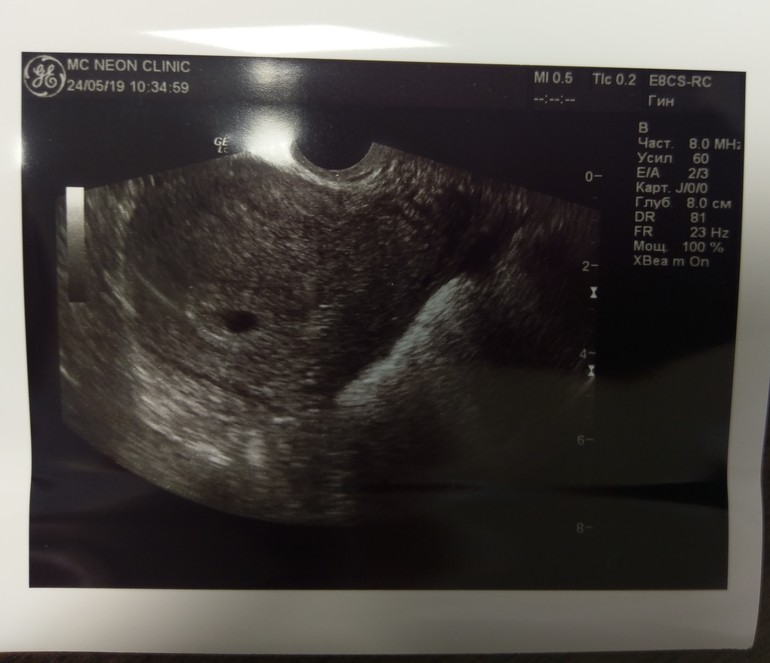

Пошли на узи. И тадааам, ПЯ в домике 5мм.